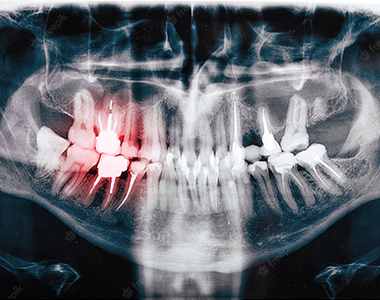

Early tooth decay does not tend to show many physical signs. Sometimes the tooth looks healthy, but your dental team will be able to see from an x-ray whether you have any decay under the enamel, any possible infections in the root, or any bone loss around the tooth.

X-rays can help the dental team to see in between your teeth or under the edge of your fillings. Finding and treating dental problems at an early stage can save both time and money.

In children, x-rays can be used to show where the adult teeth are and when they will appear. They are also used in the same way for adults when the wisdom teeth start to come through.

X-rays can show decay that may not be seen directly in the mouth: for example, under a filling, or between the teeth. They can show whether you have an infection in the root of your tooth and how severe the infection is.

In children, an x-ray can show any teeth that haven’t come through yet, and show the dental team whether there is enough space for the teeth to come through. In adults, it can show any impacted wisdom teeth that may need to be removed, before they cause any problems.